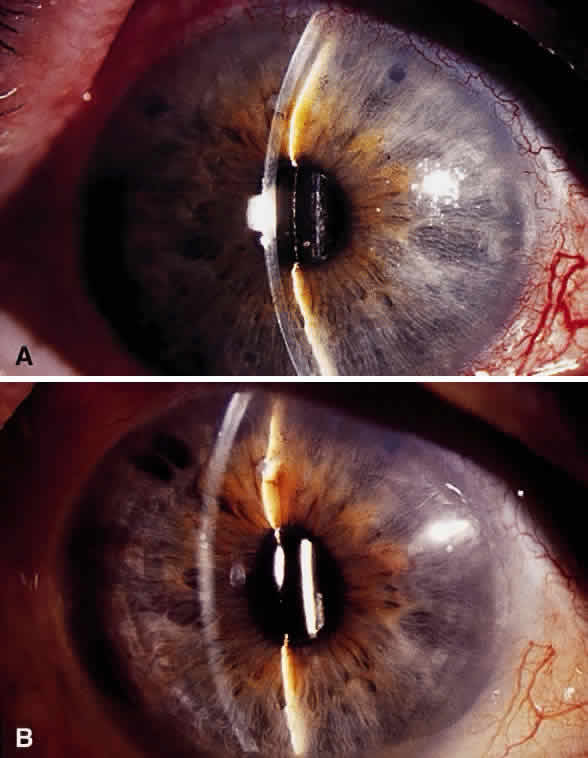

Postoperative suprachoroidal hemorrhage usually occurs within the first week after glaucoma surgery and usually is associated with postoperative hypotony4–6 (Fig. 1). The development of a suprachoroidal hemorrhage typically is acute and associated with the sudden onset of severe pain. Examination of the anterior segment frequently reveals a shallow anterior chamber and a normal or high intraocular pressure (IOP). On fundus examination, a detached and dark choroid is noted. The choroidal elevations have a dark, reddish brown color. Some patients present with bleeding into the vitreous cavity and, uncommonly, retinal detachment. Ultrasonography can be used to diagnose suprachoroidal hemorrhage when fundus examination is not possible.

Treatment of postoperative suprachoroidal hemorrhage is directed toward control of the IOP and relief of pain. Most of these eyes do well with this conservative management, and surgical drainage usually is not necessary.8 The indications for drainage include intolerable pain, a persistent flat anterior chamber, and massive “kissing” choroidal detachments (see later). A waiting period of about 7 days after a suprachoroidal hemorrhage is advised for the fibrinolytic response to liquefy the clot and allow for more effective evacuation of the suprachoroidal space. Drainage through a sclerotomy into the suprachoroidal space reveals liquefied blood, which usually is red or black. Occasionally, the fluid drained is a mixture of clear, straw-colored fluid and reddish to black liquefied blood. Bleeding into the vitreous cavity at the time of the hemorrhage and retinal detachment worsen the visual prognosis.